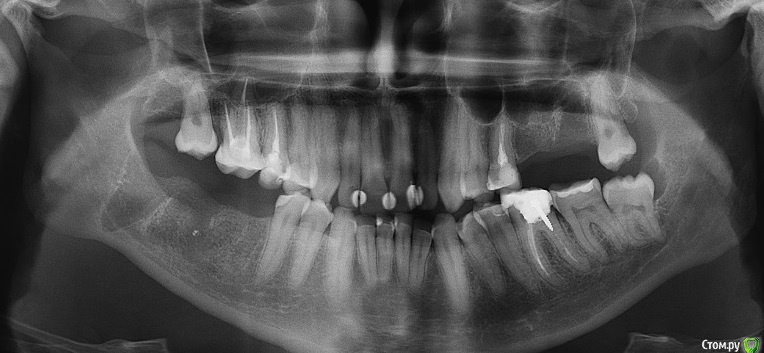

kuznetsovaev Опубликовано 19 октября, 2015 Поделиться Опубликовано 19 октября, 2015 (изменено) Добрый вечер, уважаемые врачи, подскажите мне пожалуйста какой вариант имплантации более правильный. Буду очень надеяться на вашу помощь. Так же буду рада если будут еще какие-то может более верные варианты. Заранее благодарю. Были кисты на верхней и нижней челюсти, в связи с чем удалили зубы.КТ от 10.10.2015г. Мне 33, пол женский.Верх лево: 7зуб и киста над ним удалены 18.09.2015, соседний 6-ой удален 3года назад.Низ право: 6-ой зуб удален 20.04.2015, киста и 7-8 зубы удалены 13.08.2015г. Пока хожу по клиникам ищу "своего" врача и слышу разные мнения. Вариант 1.1. Нижние 6 и 7 импланты ставить без костной пластики через пару месяцев (в декабре), кость сама нарастет. Сделать прицельный снимок перед имплантацией и все, т.к. очертания кости уже видны, кость просто станет более плотной, а границы уже не изменятся.2. Верхние 6 и 7 ставить через полгода после синуслифтинга. Вариант 2.1. Нижний 6 без костн.пластики, а в 7 лунку пересадить свой костный материал закрепив минигвоздиками (если правильно запомнила). Спустя три месяца ставить импланты сразу в 6 и 7.2. Верх синуслифтинг над 6 и 7кой, через полгода ставить и 6 и 7 имплантат. В этом варианте прозвучала еще мембрана и 4 болтика, я не поняла куда ее крепить будут. Вариант 3.1. Низ 6 готова к имплантации, а в 7ку засыпать микс кости моей и инородной. Спустя два-три месяца ставить импланты сразу в 6 и 7.2. А на верхней челюсти над 6-ой подъем пазухи, а над 7-кой не надо поднимать, а нужно засыпать в ее лунку смесь моей и инородной кости, закрыть мембраной. Ну и через полгода имплантация. Вариант 4.1. Внизу без костной пластики.2. Верх через закрытый синус досыпят кости с одновременной имплантацией. Изменено 19 октября, 2015 пользователем kuznetsovaev Ссылка на комментарий